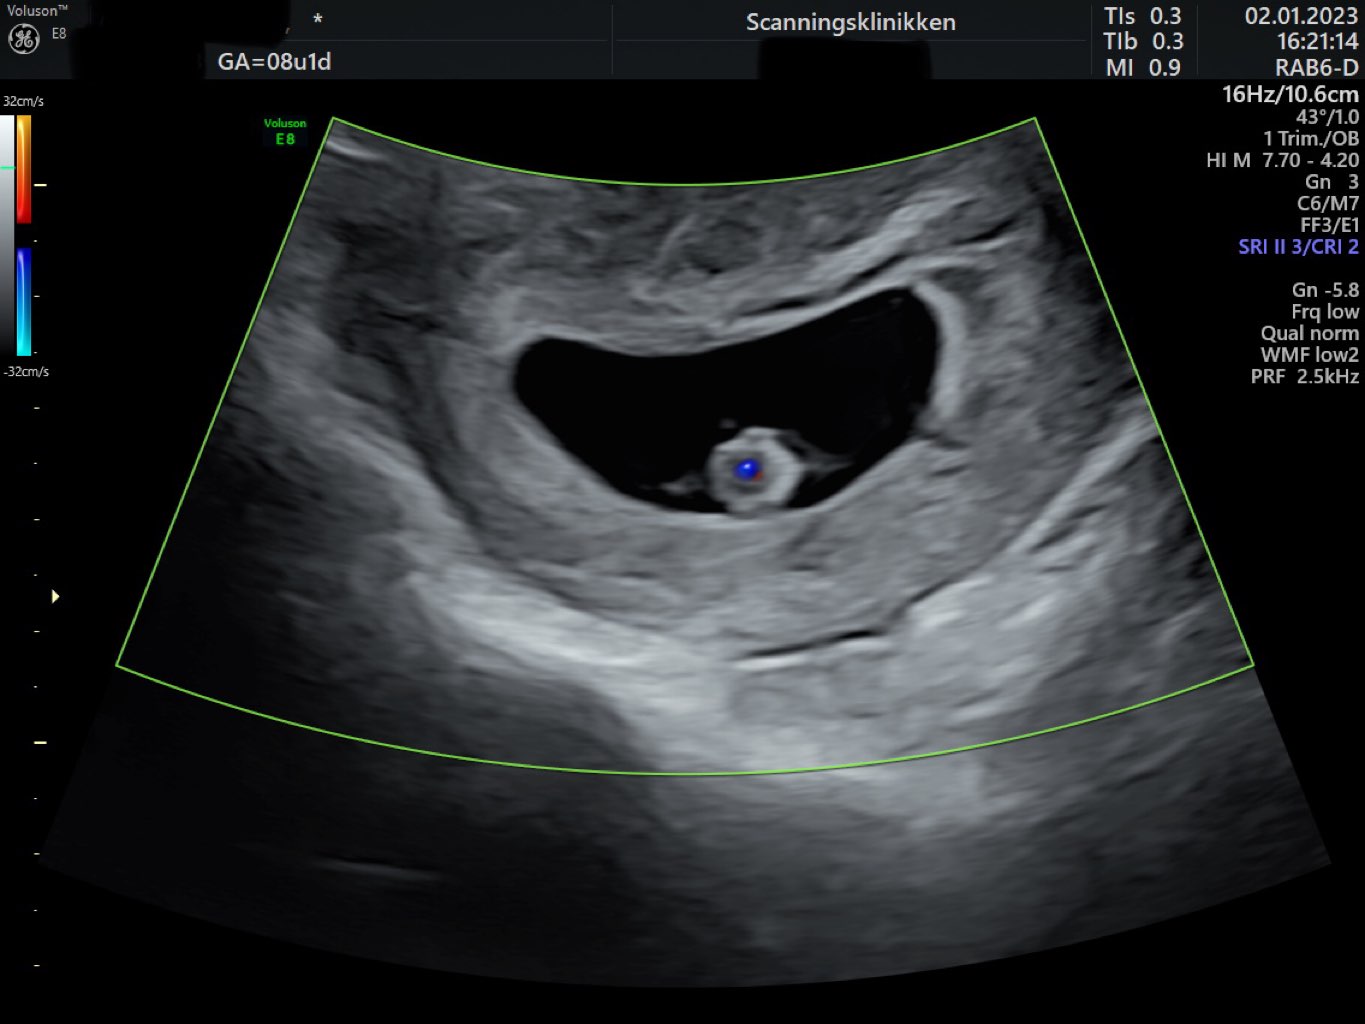

Cudowne wieści ❤️🫶🏻🔥! Ja właśnie wróciłam do domu..u mnie to 7+4 i też wszystko dobrze 🥹❤️. Maleństwo mierzy 1,28 cm 🥰.

@Paulusman Termin porodu mam obecnie na 17.08 a prenatalne 26.01 🥰

• IMG_5714.jpeg

IMG_5714.jpeg

108,6 KB · Wyświetleń: 94